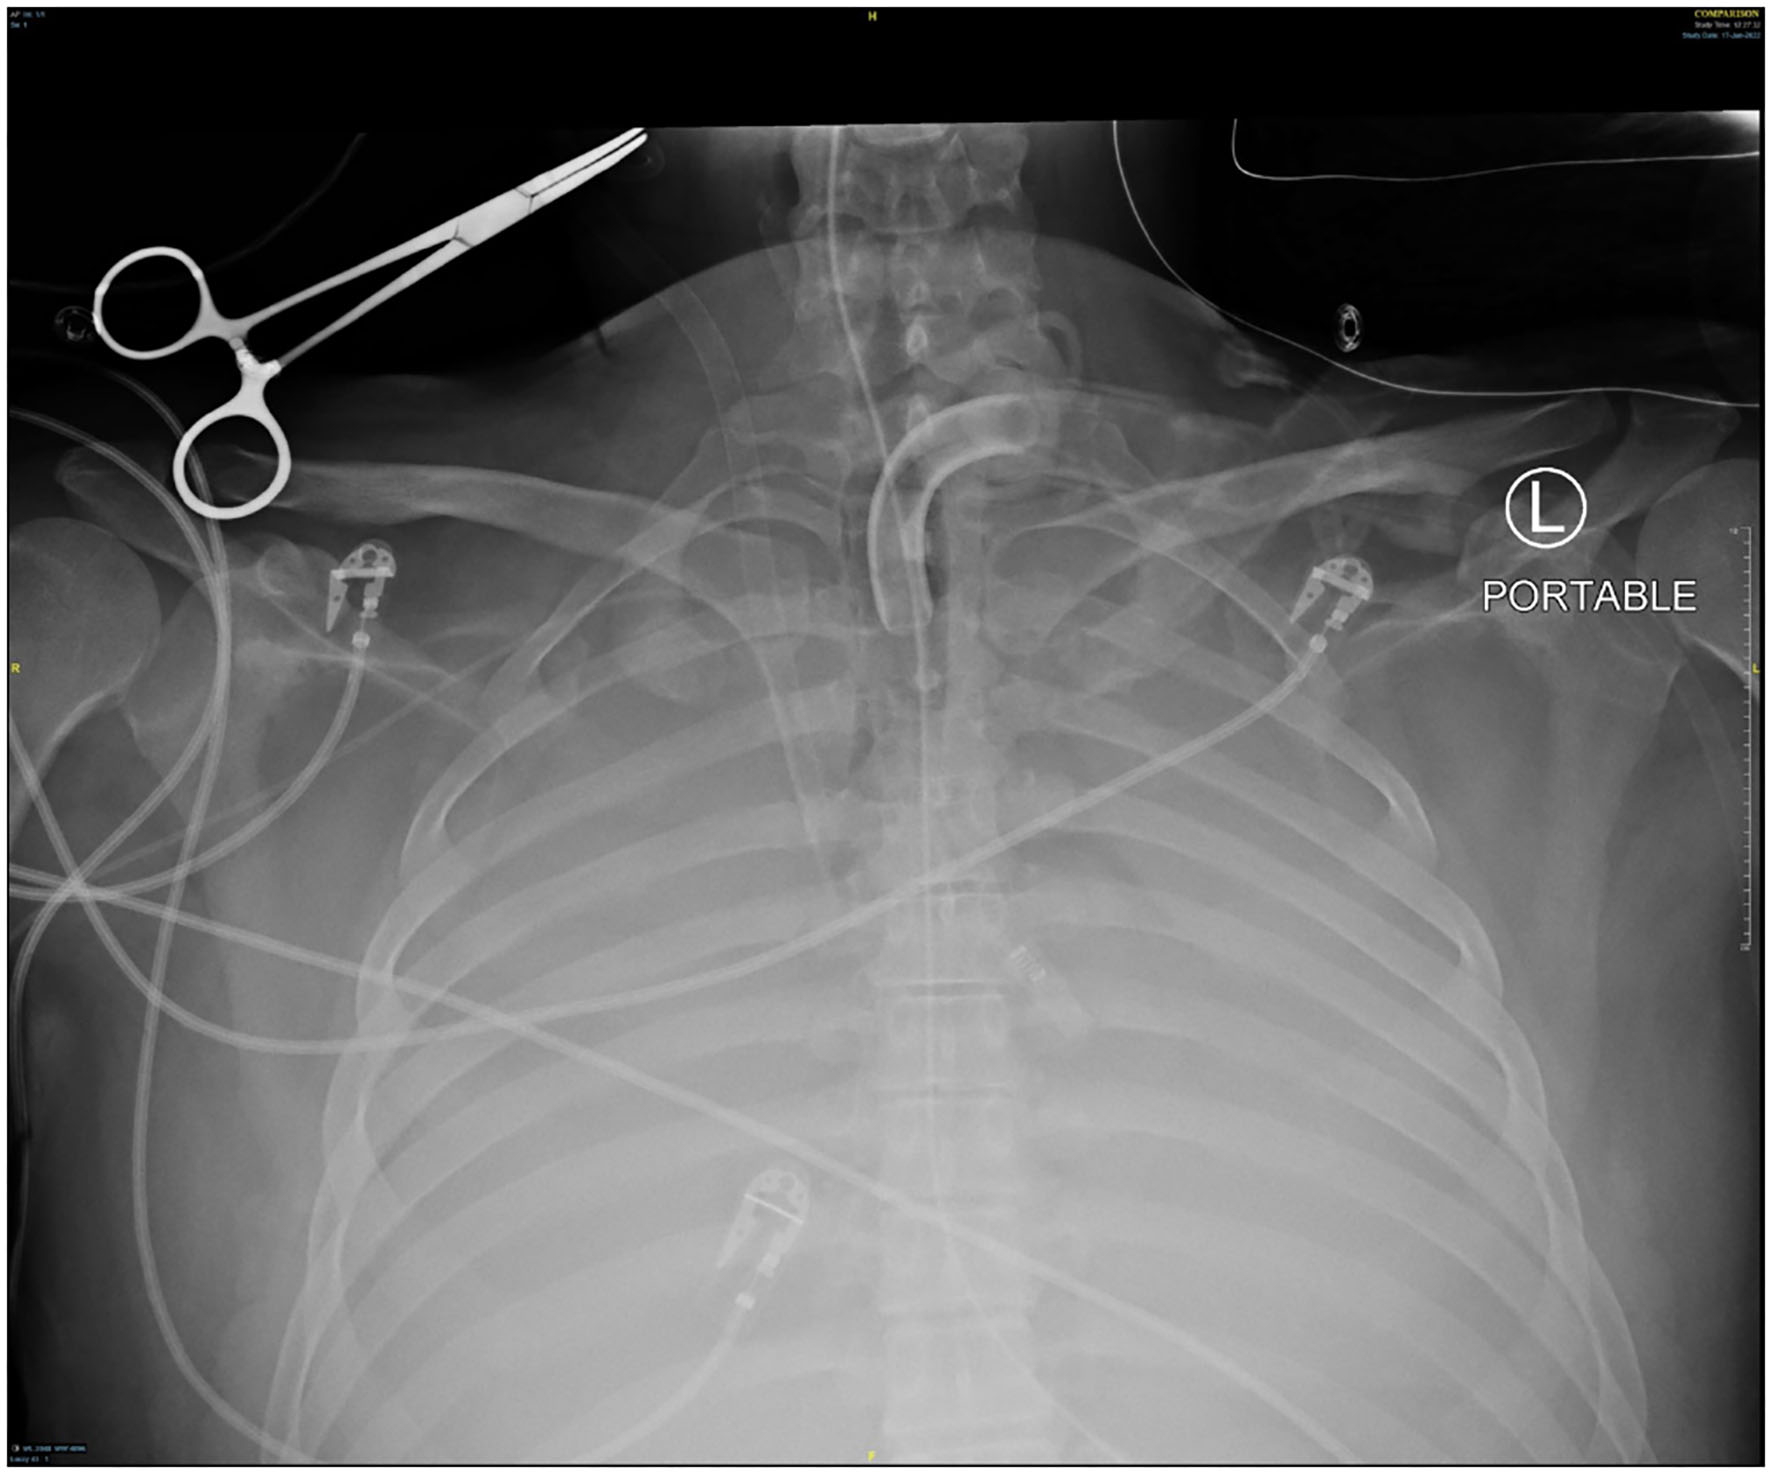

Figure 1

Chest x-ray at the time of hemoptysis.

Several days after tracheostomy (hospital day #18, VV ECMO day #11) hemoptysis developed and it persisted despite holding heparin drip and normal platelet counts. His chest x-ray demonstrated bilateral opacifications (Figure 1). Dark blood was suctioned continuously from the tracheostomy and hemoglobin repeatedly dropped requiring transfusions. VV ECMO settings were increased to 100% FiO2 as the VV ECMO sweep was maximized to 11 L/min to maintain SpO2 >85%. Bedside bronchoscopy revealed massive bleeding in the left and right main bronchi. Ice cold saline and epinephrine lavage failed to control the bleeding, thus the site of bleeding was unable to be identified. Despite the evacuation of more than 500 cc of blood under bronchoscopy, there was continued hemorrhage from both main bronchi (Figure 2). The tracheostomy tube was removed to examine the stoma, and no active bleeding was identified in that area. A direct suction was then attempted, inserting a Yankauer suction catheter into the trachea via the tracheostomy stoma (Figure 3). This was also unsuccessful in clearing the airway. In further attempts to control bleeding, continuous bronchoscopy was performed for 4 h with the maintenance of adequate SpO2 >85% despite discontinuation of the ventilator.